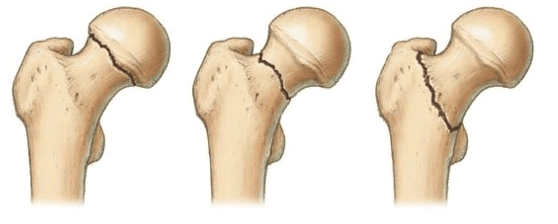

Выделяют несколько разновидностей переломов:

Тип 1: абдукционный, субкапитальный, неполный перелом без смещения. Происходит он вследствие действия отводящих натяжений. Шейка и диафиз бедра при переломе направлены в сторону головки. Костные фрагменты крепко вклинены, и линия поверхности перелома приближена к горизонтальной. Нарушение кровоснабжения минимальные (до 10,2%). Прогноз на выздоровление хороший.

Слева-направо: субкапитальный, трансцервикальный, базисцервикальный переломы.

Тип 2: аддукционный, субкапитальный, полный перелом без смещения. Перелом расположен в вертикальной плоскости, проходит через шейку бедра. Трабекулы и нижний корковый слой разорваны, без смещения. Микроциркуляция нарушена на 23,6%. Прогноз благоприятный.

Тип 3: аддукционный перелом с неполным смещением костных структур. Он характерен варусной деформацией шейки бедра, но фрагменты остаются соединенными за счет задне-нижнего блока. Дистальный костный фрагмент - в положении наружной ротации и отведения с углом, открытым кпереди. Имеется оскольчатый перелом задней поверхности шейки. Трабекулы и нижний кортикальный слой разорваны. Нарушение васкуляризации достигает 42,8%. Риск развития асептического некроза.

Тип 4: аддукционный перелом с полным смещением. Головка лишается всех связей с синовиальной оболочкой капсулы, в результате чего фрагмент становится свободным. Нарушение кровоснабжения максимальное (54,4%). Риск образования асептического некроза повышенный.